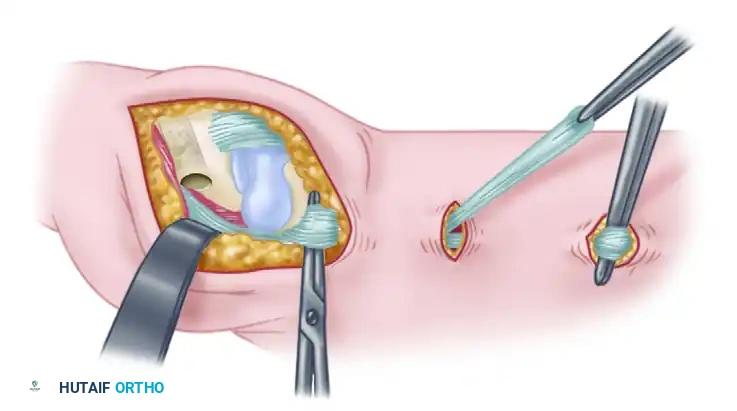

- Bone Tunnel Creation: Using a 4-mm rough burr, create holes through the base of the thumb metacarpal, directing them proximally and radially. Connect these holes using a series of curets (usually up to a No. 2) to form a smooth, continuous tunnel.

Figure A: Holes made in the thumb metacarpal base following trapeziectomy.

Intraoperative view of the trapezial void and preparation of the metacarpal base.

- Tendon Passage: Pass the harvested FCR tendon strip through the newly created bone tunnel. Hold the tendon perpendicular to the index metacarpal shaft.

- Suspension: Approximate the index and thumb metacarpal bases by applying slight ulnarly directed pressure on the thumb metacarpal. Firmly secure the FCR tendon to the APL bony insertion using 2-0 braided nonabsorbable sutures. This step acts as a "suspensoplasty," preventing proximal migration of the thumb metacarpal.

Figure B: FCR tendon passed through the bone tunnel while the index and thumb metacarpal bases are approximated.